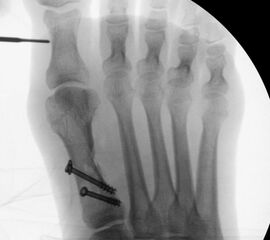

• Kanülierte Schrauben bis 50 mm Länge, 4 mm Durchmesser, Beilagscheiben.

• Akkubohrmaschine, Kirschnerdrähte.

• Bruch der medialen Kortikalisbrücke mit Verkürzung und Elevation des 1. Strahles. In diesem Fall muß die Länge des 1.Strahles durch eine quer zur Schaftachse plazierten Schraube gesichert werden. Als Alternative bietet sich eine lange Schraube durch den Schaft als intramedullärer Kraftträger an